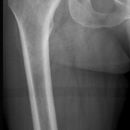

• Knie und Hüftgelenk mitbeurteilen! (2-5% mit ipsilateralen Schenkelhalsfrakturen.)

• Postop: Abbildung der Implantatenden. Marknägel sollten das proximale Ende des Trochanter major nicht überragen. Schrauben und Platten sollten in einer Ebene exakt seitlich dargestellt sein. Achsengerechte Stellung der Hauptfragmente.

Cave: Signifikante Beinlängendifferenzen (>2cm) und Rotationfehler (> 20 °)

Diaphysenfrakturen: direkte Gewalteinwirkung durch Rasanztraumen (Cave v.a. in Kombi mit proximale Femurfraktur). Einteilung nach AO.